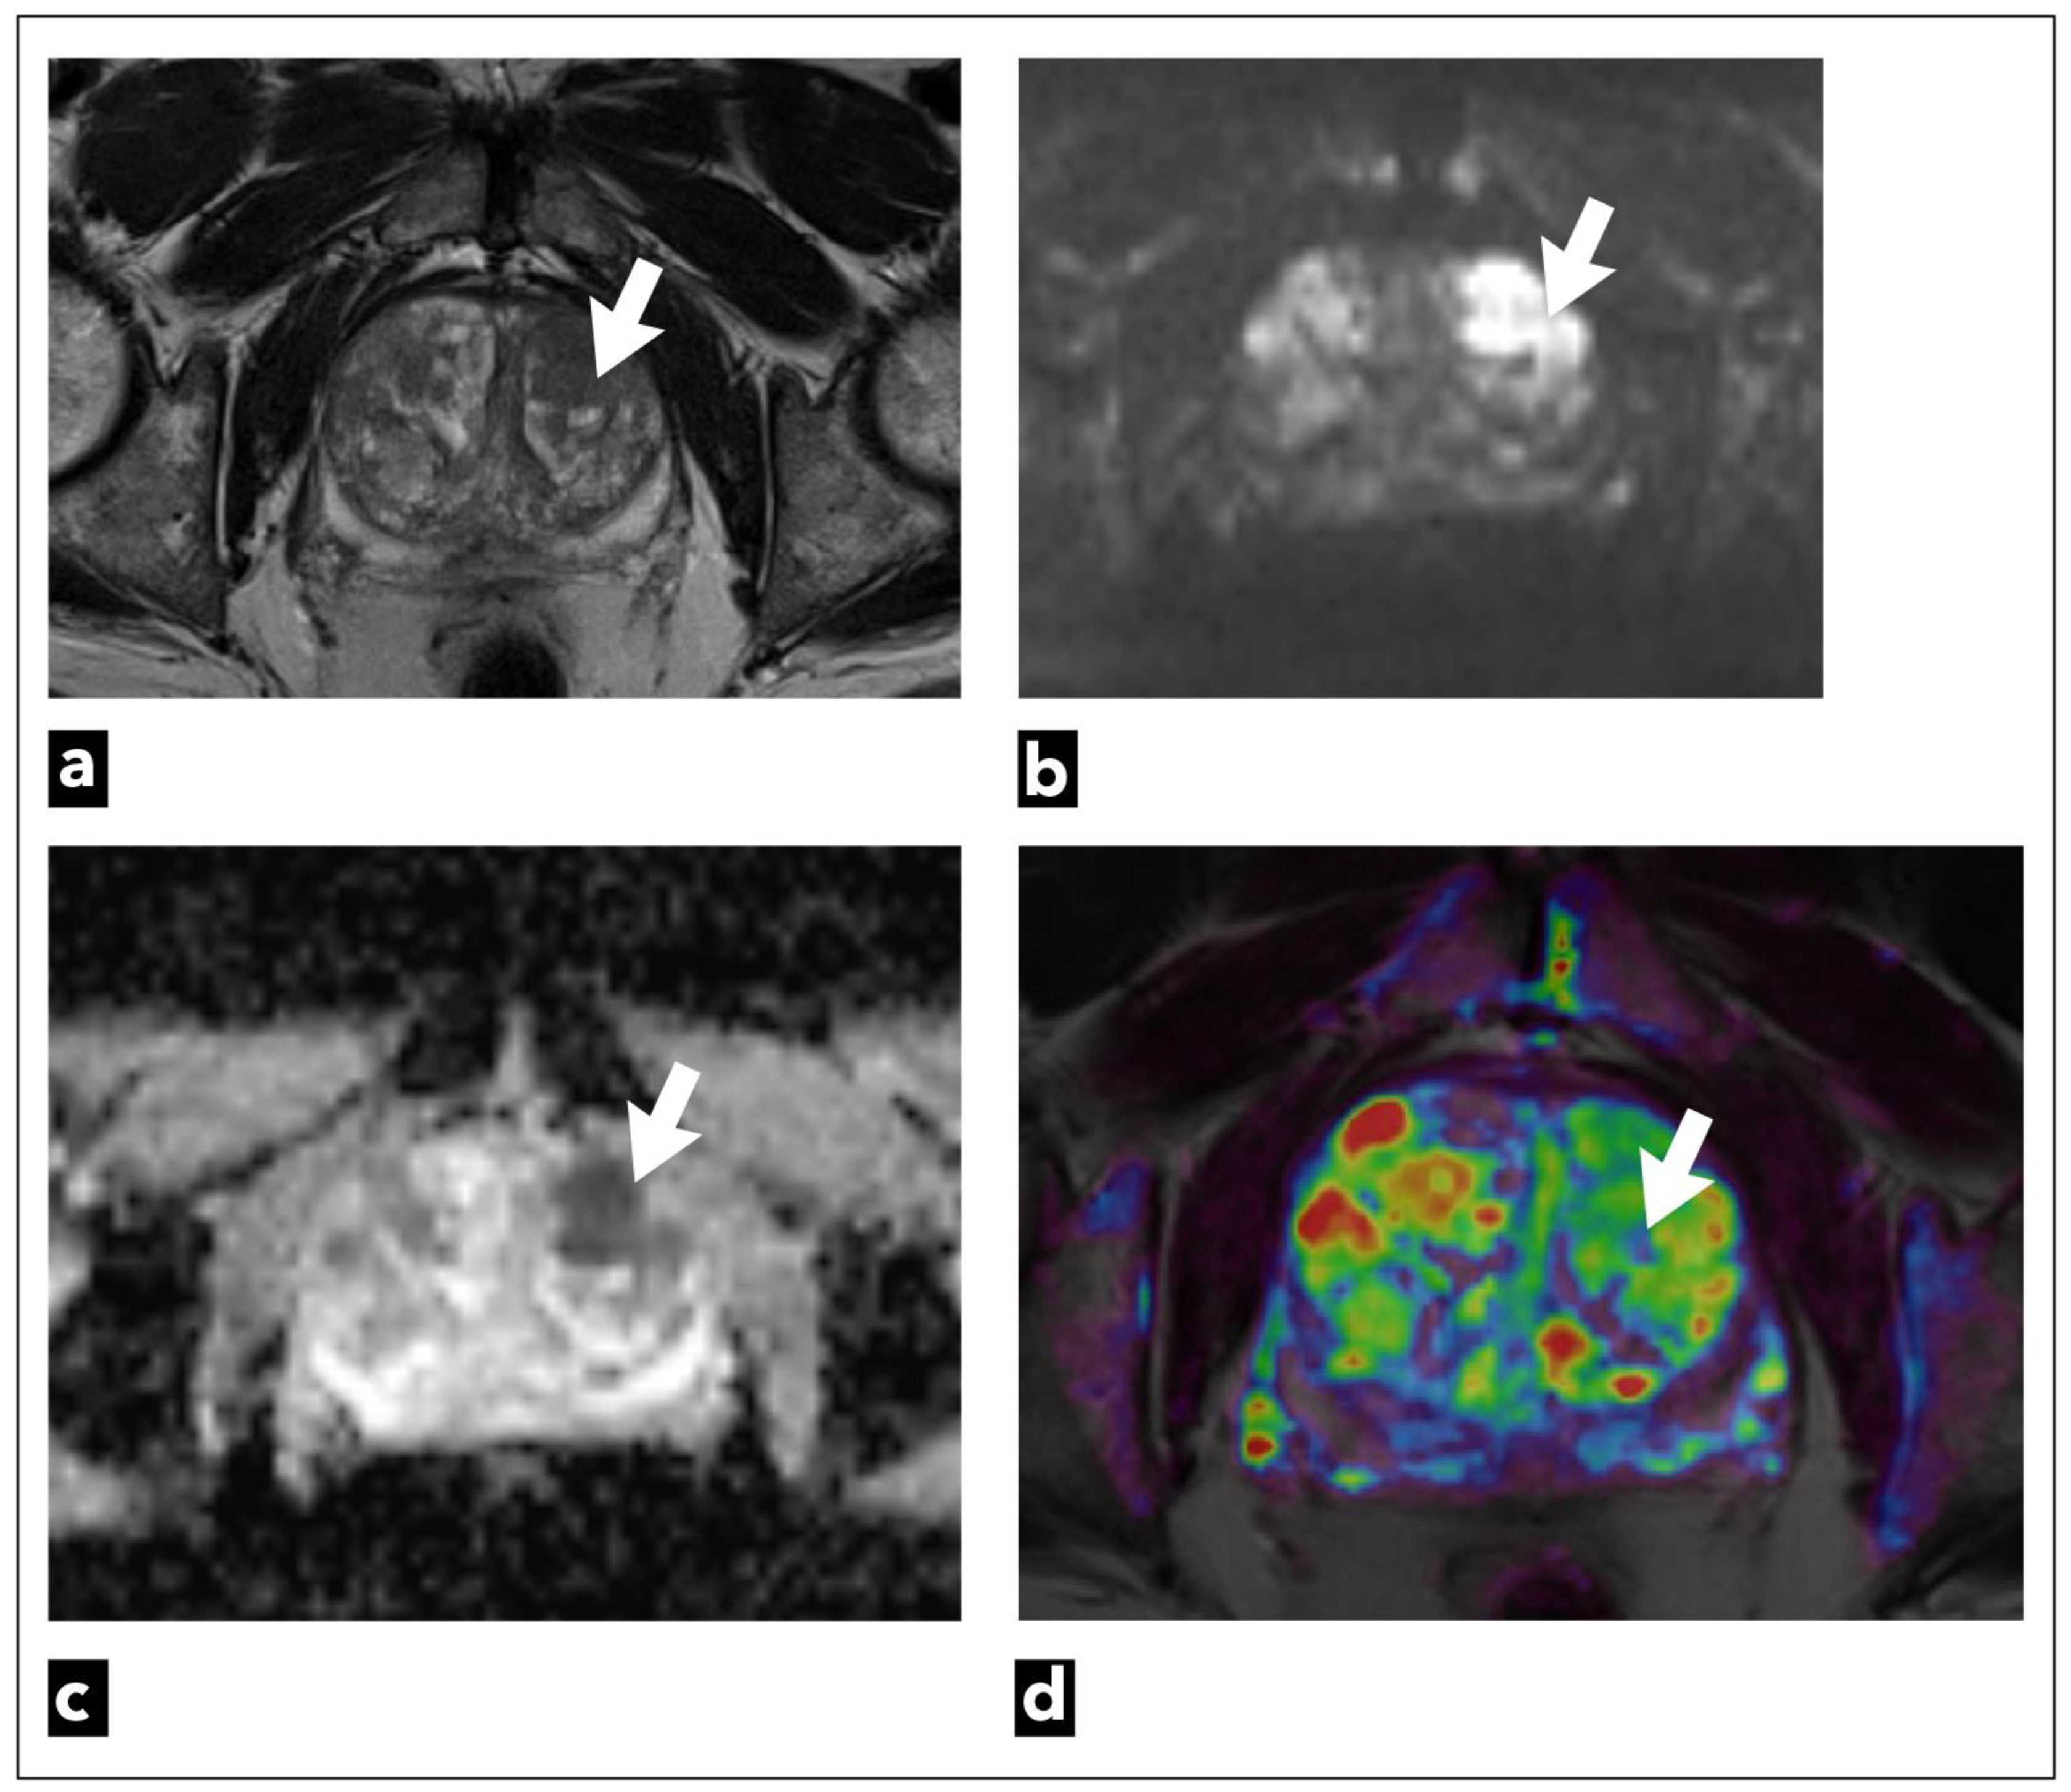

Another scoring system, in which DCE plays a much more important role, is called Prostate Imaging for Recurrence Reporting (PI-RR). It was suggested by experts from the European Society of Urologic Imaging, the European Society of Urogenital Radiology, and members of the Prostate Imaging-Reporting and Data System (PI-RADS) Steering Committee in 2021 [89].

PI-RR is a scoring system that estimates the probability of prostate cancer local recurrence following radiation therapy (RT) (Figure 5) or radical prostatectomy (RP) (Figure 6).

The most common location of prostate cancer recurrence after radiation therapy is the primary prostate cancer location [90]. Radiation therapy can result in dramatic changes in the prostate gland morphology, anatomy, and signal intensity seen on T2W sequences due to fibrosis, inflammation, or atrophy [91]. For those reasons, T2W sequences are used only for the anatomical orientation and precise location of detected suspicious lesions in detecting prostate cancer recurrence after radiation therapy, but do not play a part in deciding the final score [89]. DWI and DCE sequences have the key role in determining the final PI-RR score, and the sequence that has a higher score determines the final score [89,92]. DCE-MRI shows recurrent prostate cancer as a hypervascular lesion due to the formation of new vessels with increased vascular permeability [93].

The drawback of DCE-MRI is the fact that if it is performed within the three months following RT, radiation-induced inflammatory changes result in falsely positive hypervascular areas [89,94].

DCE-MRI plays a crucial role as a dominant sequence in detecting prostate cancer recurrence after radical prostatectomy [89,92]. Prostate cancer recurrence is characterised by early arterial enhancement with an early wash-out that is easily visible on DCE-MRI, while there is slow or no enhancement in postoperative cicatricial and granulation tissue [95]. In postoperative PI-RR scoring, T2W also has a role only in anatomical and morphological assessment, and DWI has the secondary role in upgrading the score PI-RR 2 to PI-RR 3 and PI-RR 3 to PI-RR 4 when the DWI score is ≥4 [89,92]. Also, DCE is of limited value in the first three months after a radical prostatectomy [89], as well as in post-radiation imaging assessment, which are its major disadvantages. Studies have observed the benefit and superiority of DCE-MRI compared to T2W sequence in the detection of prostate cancer residue or recurrence [96,97]. Haidar et al. observed that the dynamic contrast study has a sensitivity of up to 72%, a positive predictive value of up to 46%, and a negative predictive value of up to 95%. In comparison, the T2 sequence has a sensitivity of up to 38% when detecting recurrence/residue after radiotherapy in the peripheral zone, a positive predictive value of up to 24%, and a negative predictive value of up to 88% [96].